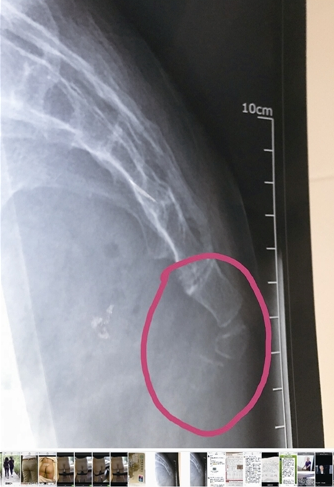

CT检查显示陈女士尾骨受伤

8月初,陈女士在温州医科大学附属第二医院做腰背部X射线、CT等检查,检查报告显示,陈女士腰椎多处膨出、突出,骶尾椎的“尾3”部位滑移。